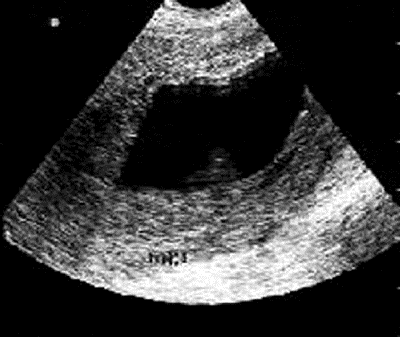

Для подтверждения замершей беременности осуществляется объективный осмотр пациентки. Удается установить отсутствие увеличения матки. Также больной назначается анализ крови на содержание гормона ХГЧ. При замирании беременности его уровень снижается и не соответствует показателям, которые свойственны для данного срока эмбриогенеза. Инструментальная диагностика заключается в проведении ультразвукового сканирования маточной полости. При замершей беременности отсутствуют любые признаки жизнедеятельности плода (двигательная активность, биение сердца).